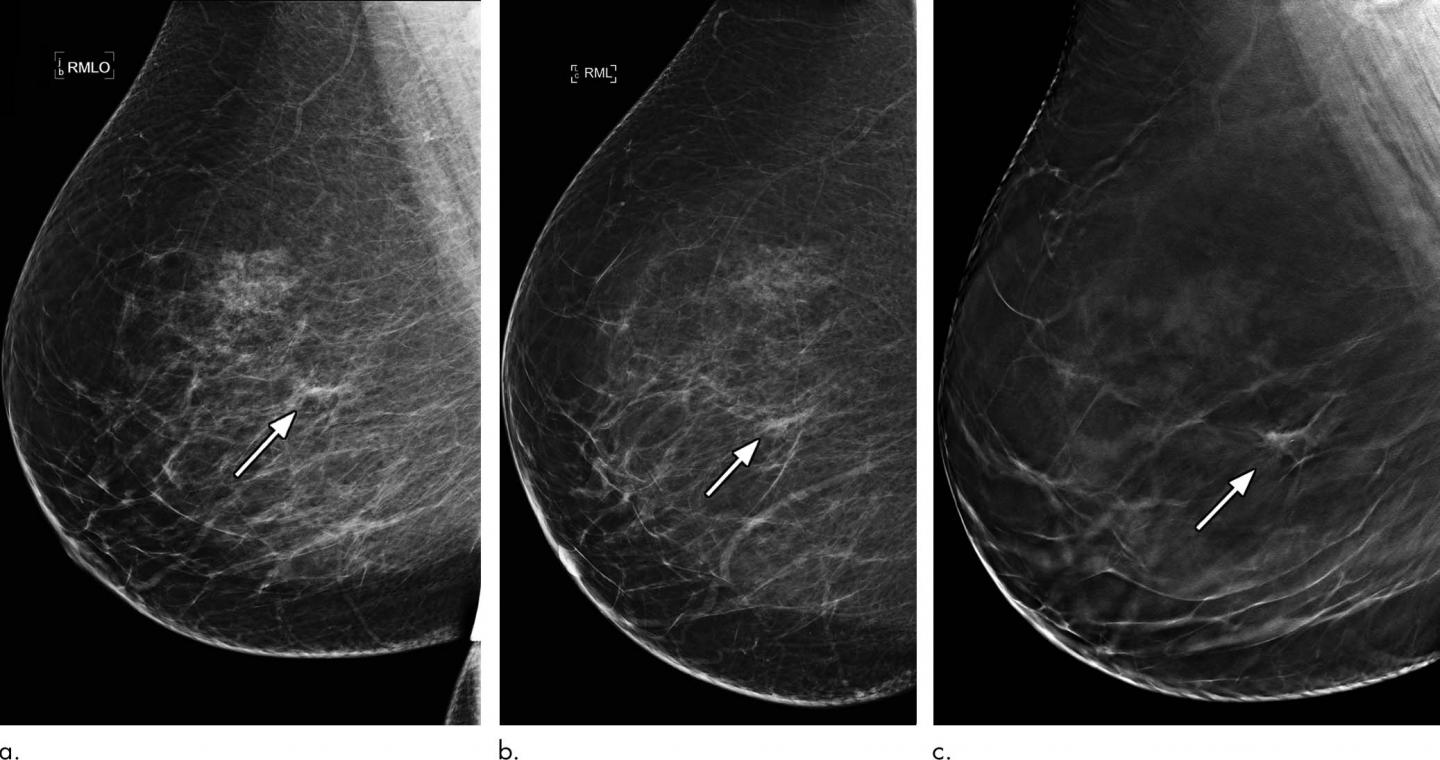

OAK BROOK, Ill. - The use of digital breast tomosynthesis (DBT), also known as 3-D mammography, may significantly reduce the number of women who undergo breast biopsy for a non-cancerous lesion following an abnormal mammogram, according to a new study published in the journal Radiology .

Unlike standard or full-field digital mammography (FFDM), which captures two x-ray images of the breast from top-to-bottom and from side-to-side, DBT captures multiple images from different angles that are synthesized into 3-D images by a computer.

"The thin slice images of the breast taken with DBT reduce the effect of tissue overlap, which often leads to cancers being missed or to women who don't have breast cancer being recalled for diagnostic imaging," said lead researcher Nisha Sharma, M.B.Ch.B., director of breast screening and clinical lead for breast imaging at Leeds Teaching Hospital NHS Trust, Seacroft Hospital, in Leeds, England. "In our study, we wanted to determine the impact of DBT on the biopsy rate among women recalled for an abnormal screening mammogram."